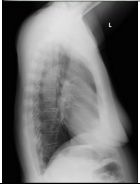

1. A 39-year-old man had this chest X-ray on his health exam. No any clinical symptoms.